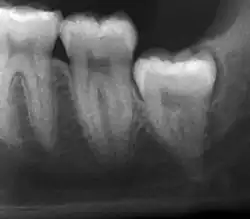

Impacted wisdom teeth are classified by their direction of impaction, their depth compared to the biting surface of adjacent teeth and the amount of the tooth's crown that extends through gum tissue or bone. Impacted wisdom teeth can also be classified by the presence or absence of symptoms and disease. Screening for the presence of wisdom teeth often begins in late adolescence when a partially developed tooth may become impacted. Screening commonly includes a clinical examination as well as x-rays such as panoramic radiographs.

If the tooth cannot be assessed with clinical exam alone, the diagnosis is made using either a panoramic radiograph or cone-beam CT. Where unerupted wisdom teeth still have eruption potential several predictors are used to determine the chance of the teeth becoming impacted. The ratio of space between the tooth crown length and the amount of space available, the angle of the teeth compared to the other teeth are the two most commonly used predictors, with the space ratio being the most accurate. Despite the capacity for movement into early adulthood, the likelihood that the tooth will become impacted can be predicted when the ratio of space available to the length of the crown of the tooth is under 1.[6]: 141